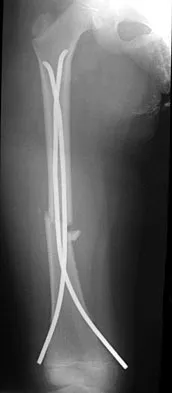

A 9-year-old boy sustained a traumatic brain injury and right lower extremity trauma in an accident involving a motor vehicle and a pedestrian. Initial evaluation in the emergency department reveals an obtunded patient who is breathing spontaneously and withdraws appropriately to painful stimuli. After initial resuscitation and stabilization, a CT scan reveals a right parietal intracranial hemorrhage. Radiographs of the swollen right thigh are shown in Figures 32a and 32b. Management of the fractured femur should ultimately consist of

A child with a traumatic brain injury generally achieves significant neurologic recovery and has a more favorable prognosis than an adult. Early stabilization of fractures facilitates transportation of the child for diagnostic tests and decreases the incidence of shortening and malunion. Surgical treatment of the fracture is indicated when cerebral perfusion pressure has stabilized. Casting or traction is not the most appropriate treatment of a femoral fracture in a child of this age with a brain injury. Fracture reduction is difficult to maintain if the brain injury leads to spasticity, and transportation within the hospital for tests is more difficult. Insertion of a reamed antegrade intramedullary nail inserted at the piriformis fossa is associated with a small risk of osteonecrosis of the femoral head. The transverse femoral fracture in this patient is ideally suited for stabilization with flexible intramedullary nails. Ligier and associates treated 123 femoral shaft fractures in children with flexible intramedullary nails, including 35 patients with head injury. In one patient with hemiplegia and a urinary tract infection, a deep wound infection developed, necessitating nail removal. The remaining patients all healed without major complications. Heinrich and associates treated 78 diaphyseal femoral fractures with flexible intramedullary nails, including 14 with head injury. No major complications were reported and all fractures healed. Tolo VT: Management of the multiply injured child, in Rockwood CA, Wilkins KE, Beaty JH (eds): Fractures in Children, ed 4. Philadelphia, PA, Lippincott-Raven, 1996, pp 83-95. Ligier JN, Metaizeau JP, Prevot J, et al: Elastic stable intramedullary nailing of femoral shaft fractures in children. J Bone Joint Surg Br 1988;70:74-77. Heinrich MS, Drvaric DM, Darr K, et al: The operative stabilization of pediatric diaphyseal femur fractures with flexible intramedullary nails: A prospective analysis. J Pediatric Orthop 1994;14:501-507.